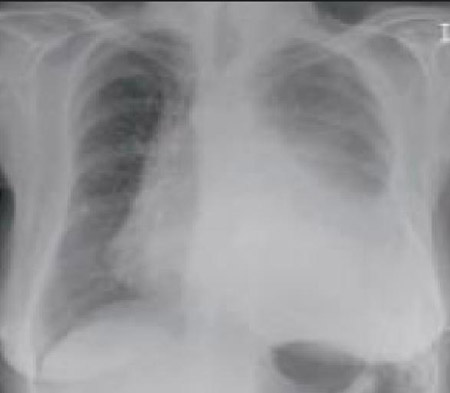

Chest x-ray in a patient with bronchogenic carcinoma showing a left-sided pleural effusion

From: R. Thakkar, Student BMJ. 2001;9:458